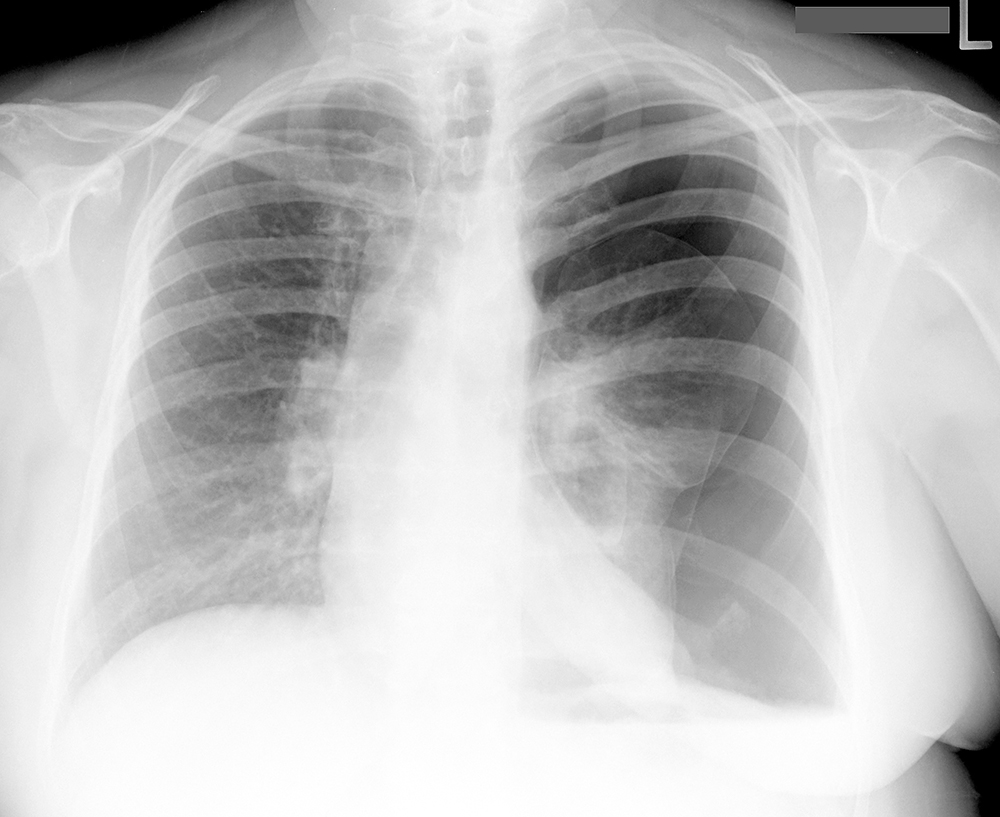

advanced case for PTX

alternative diagnosis to consider for PTX